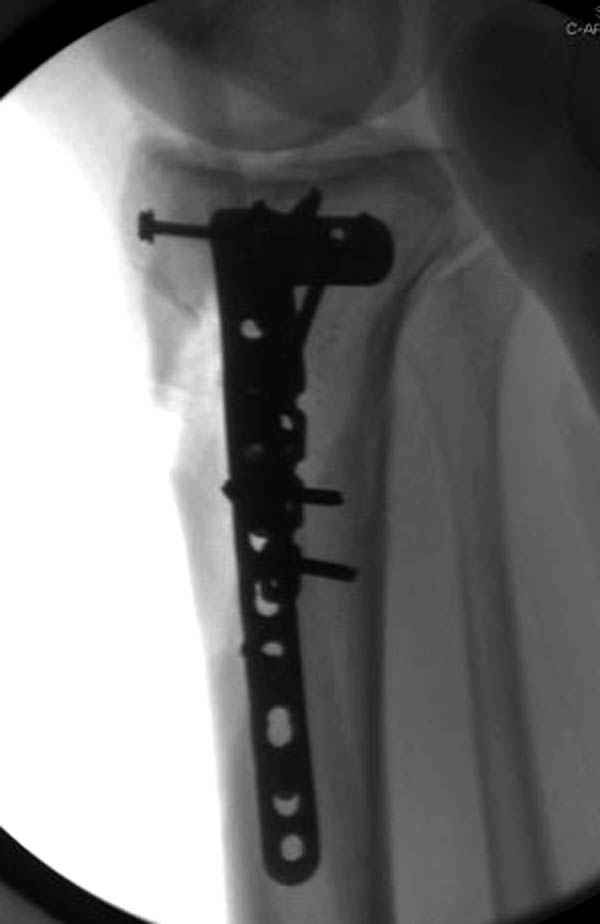

Трудно поверить, что разрекламированная Ортопедическая школа Восточной Украины позволяет такие странные снимки? На прямом снимке сохранен общий контур плато, но не известна судьба импрессии суставной поверхности. На полубоковой?, оставлен без репозиции задне-медиальный отдел, и навряд ли после такой фиксации можно удовлетвориться результатом.

Такая ситуация характерна для многих, когда принимается ошибочное решение, т.е пытаются фиксировать одним имплантом переломы двух мыщелков. Латеральная пластина приемлема только для тех случаев, когда сохраняется интактным медиальный диафизарный кортекс и отсутствует фрагментация на верхушке медиального перелома.

Здесь как раз тот случай, когда результат зависит не только от мастерства хирурга, но и от наличия современных методов исследования. Например, КТ которая поможет рассчитать направления шурупов и установку импланта. Кроме этого, поможет определиться с доступом.